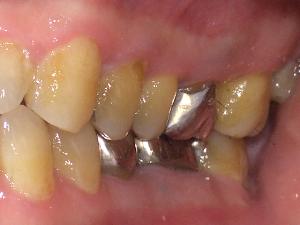

口腔内写真(口の写真)

口腔内の普段みることができかいところまでみることができます。

歯の位置、形、傾き、ブラッシングのくせ、歯肉の状態など写真で詳しく説明します。